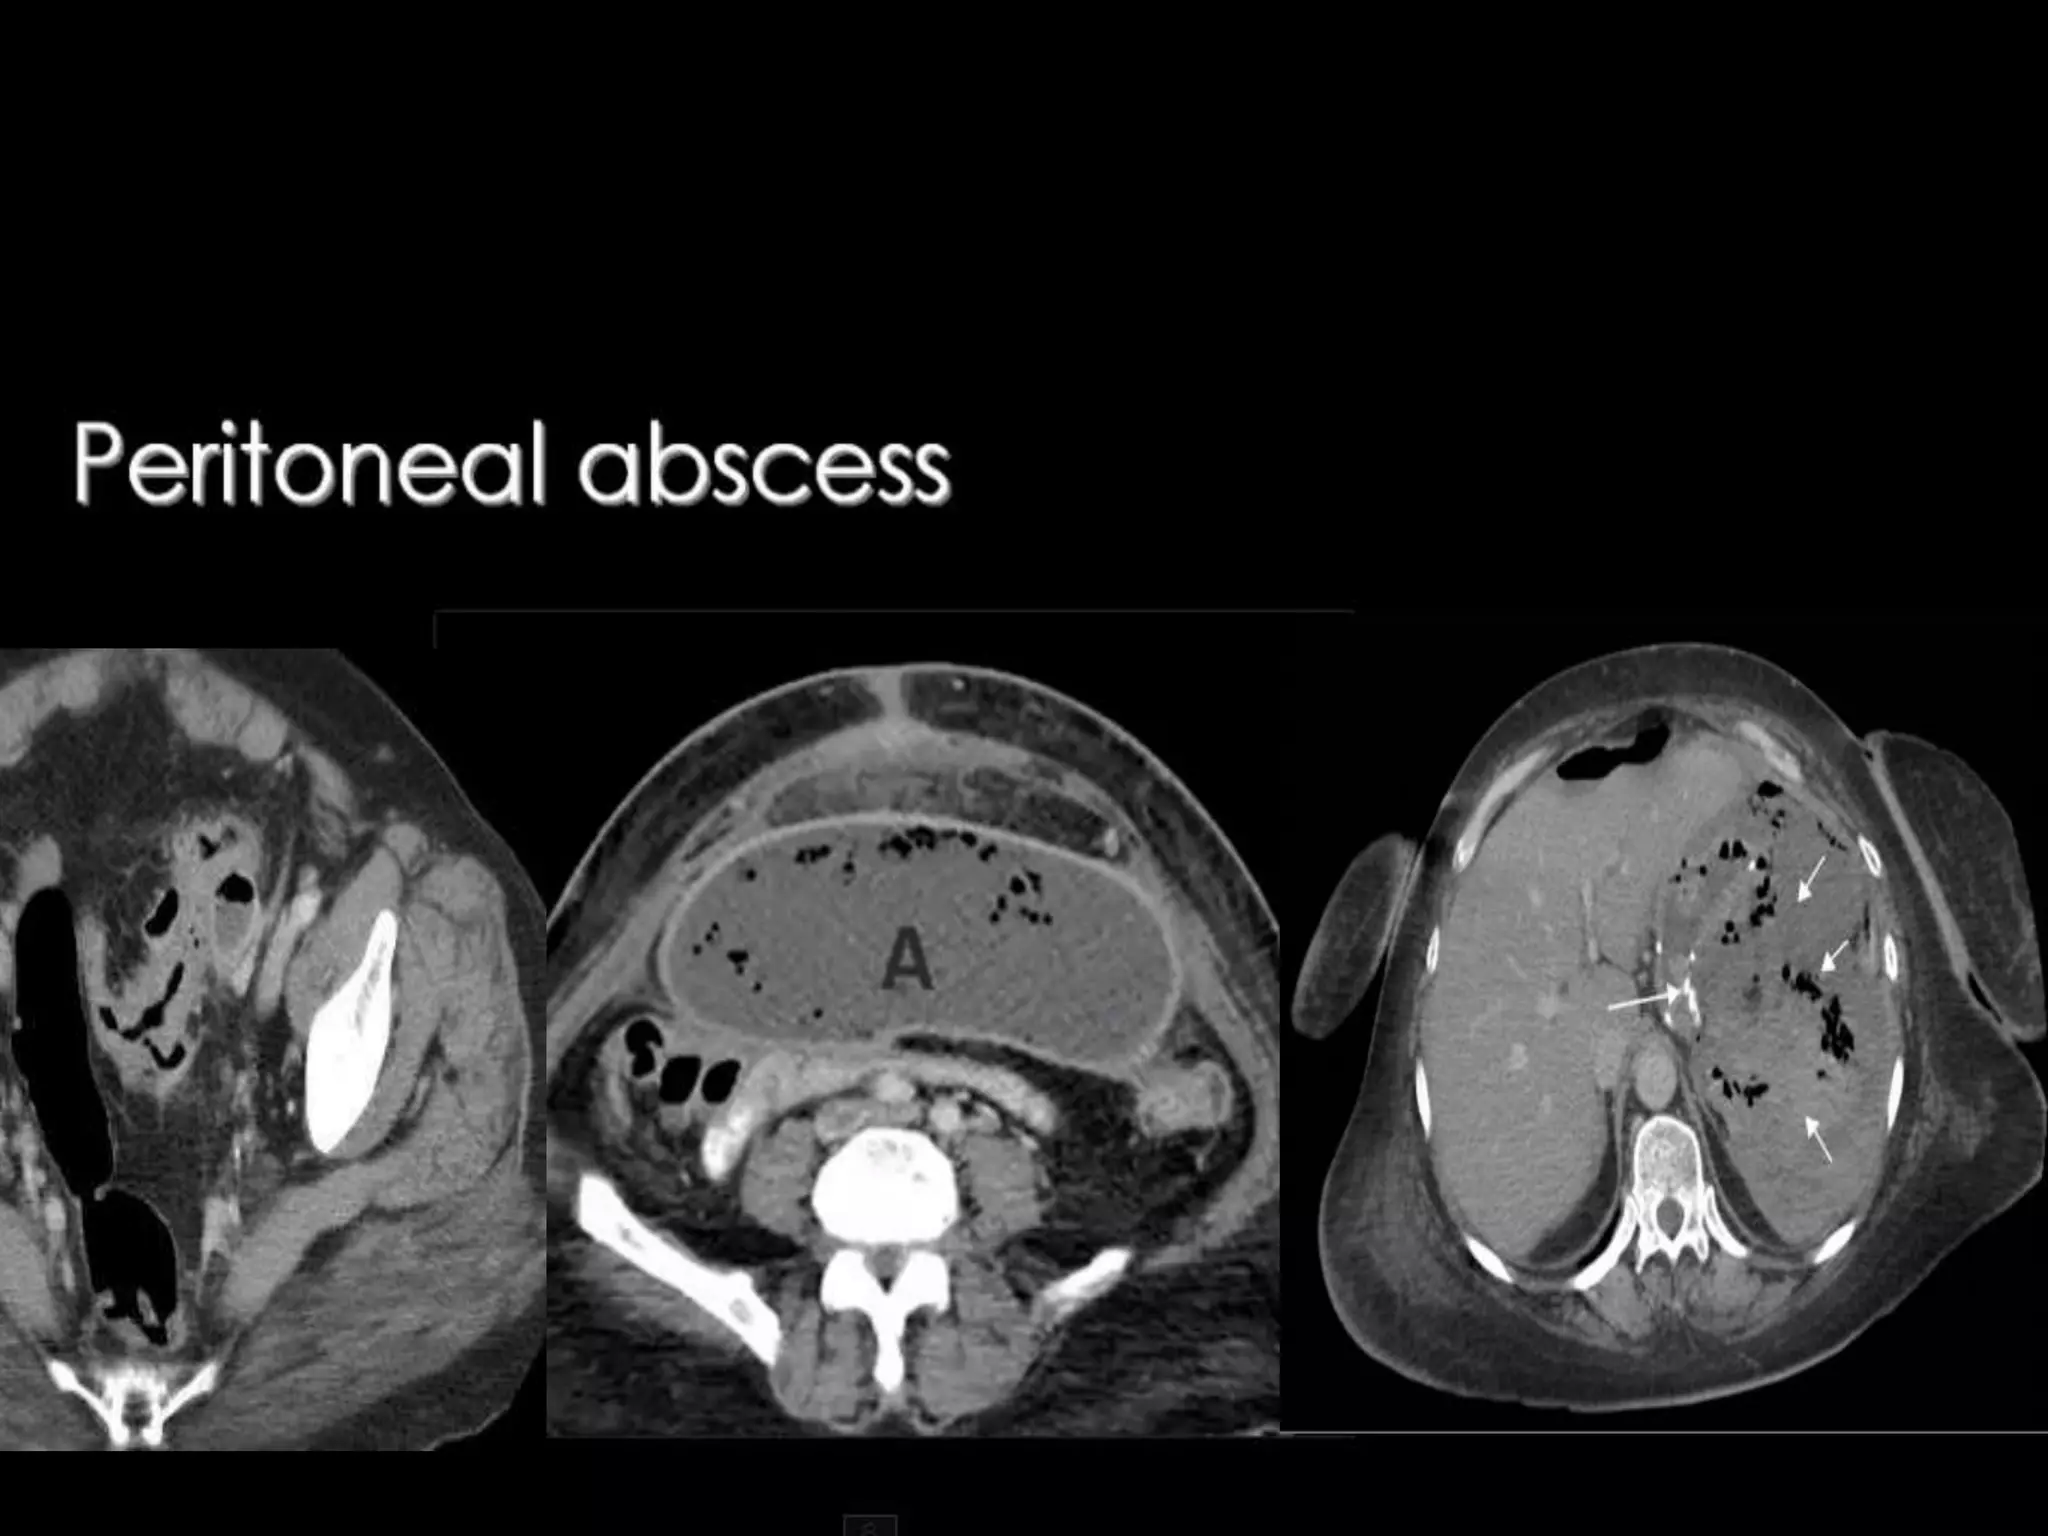

Radiological Findings